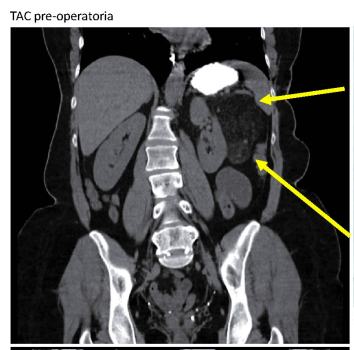

L’intervento è stato eseguito su una paziente di 54 anni che riportava una sintomatologia intestinale piuttosto vaga. L’esame TAC, praticato dopo una ecografia addominale, confermava un angiomiolipoma renale sinistro di 12 cm. La tecnica robotica ha permesso un’accurata visualizzazione dei vasi sanguigni, precedentemente dimostrati da indagini radiologiche specifiche, consentendo la selettiva chiusura di quelli patologici per evitare ischemie del parenchima renale sano, con la rimozione solo della massa, nonostante il contatto con strutture importanti come la coda del pancreas e l’arteria splenica. La donna poteva essere dimessa dopo sole 48 ore. La TC di controllo eseguita dopo 72 ore ha mostrato l’indennità del rene e la completa rimozione della malattia.